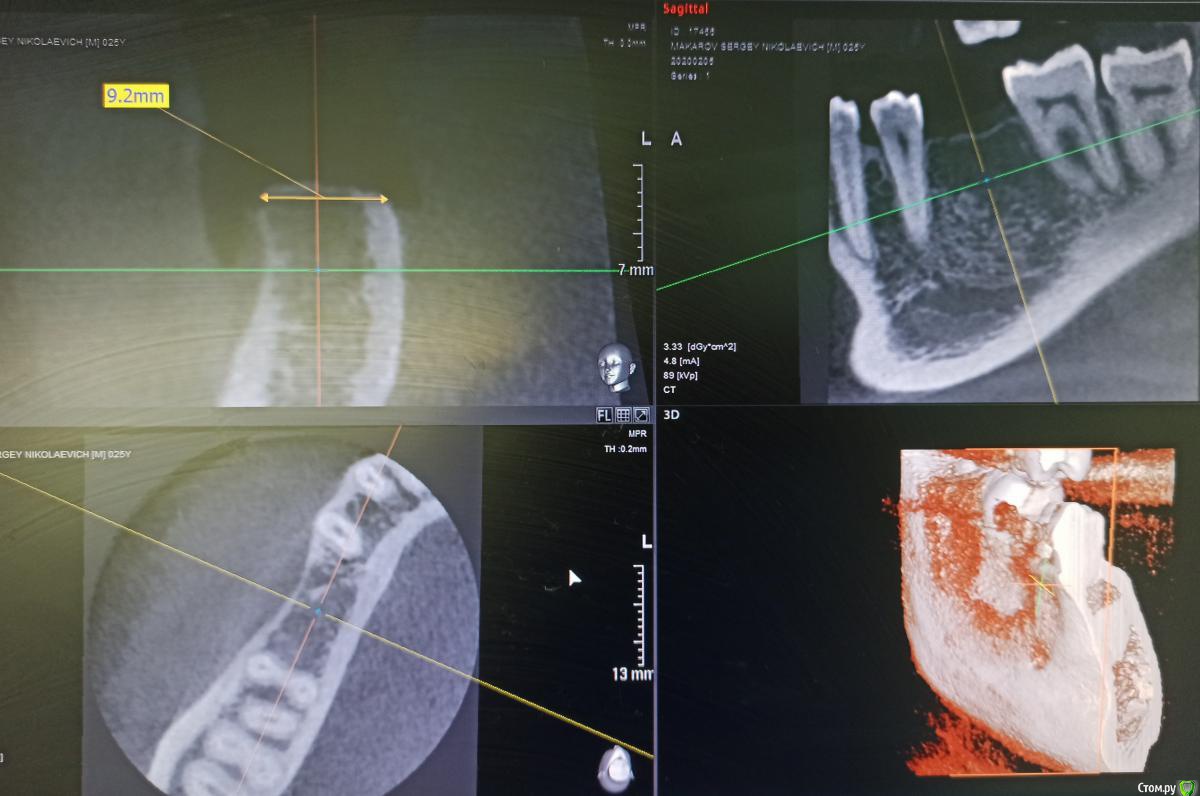

MP1121 Опубликовано 3 августа, 2020 Поделиться Опубликовано 3 августа, 2020 Добрый день! Возник небольшой спор по поводу необходимого, для имплантации, объема костной ткани.Обоснован ли в данной клинической ситуации отказ от остеопласики? И была ли в ней необходимость? Ссылка на комментарий

MP1121 Опубликовано 4 августа, 2020 Автор Поделиться Опубликовано 4 августа, 2020 Вопрос возник из-за спора с коллегой. Он считает что в конкретном случае необходимо было добавлять кость. Никакие доводы, в пользу того что ширины более чем достаточно,не принимаются. Аргументирует тем что будет эстетический(!) дефект, и нормальную коронку сделать нельзя. Имплант уже поставил Ссылка на комментарий

MP1121 Опубликовано 4 августа, 2020 Автор Поделиться Опубликовано 4 августа, 2020 Понимаю) пПциент, позвонил мне после консультации ортопеда в другой клинике, спросил почему ему даже не предложили костную пластику. Ну думаю ок, пациент что-то напутал, бывает, успокоил, попросил номер врача, созвонился и в ответ тоже самое... Я сказал что вестибулярно от шейки импланта кости миллиметра 3, и над платформой 4-5 мм. десны. Предложил узнать мнение коллег и дать ему ссылку на форум. КТ после операции не делали, но сейчас хочу направить.Не претендую на звание виртуозного хирурга, да и практикую всего два года, но такая ситуация очень неприятна. Ссылка на комментарий